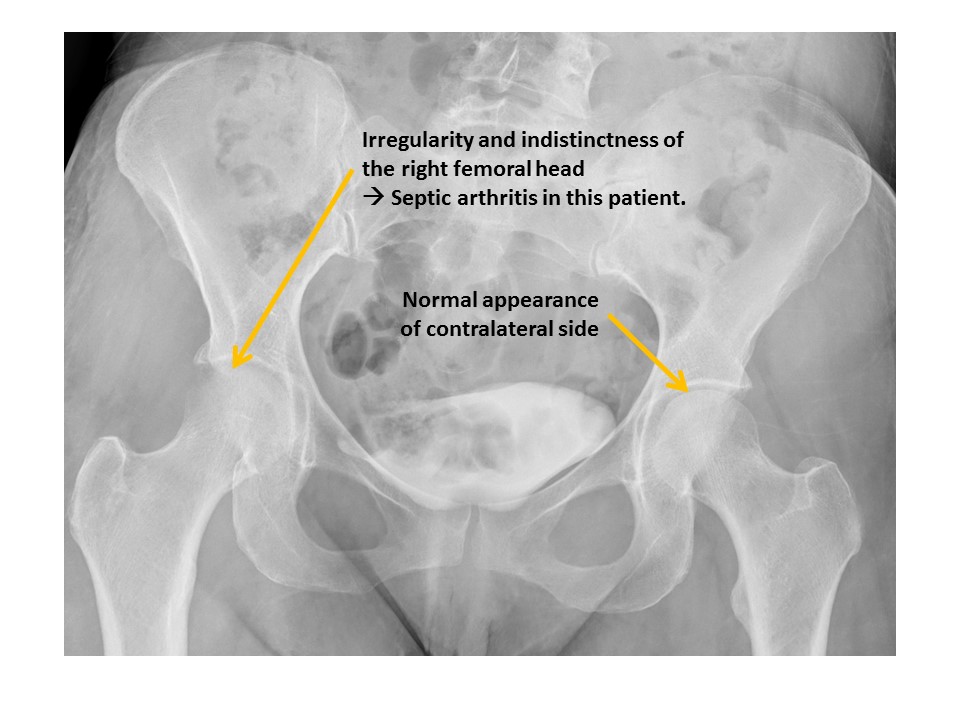

The cortices of the femoral heads are irregular. [Yes/No]

There are radiographic findings of hip osteoarthritis or inflammation. [Yes/No]